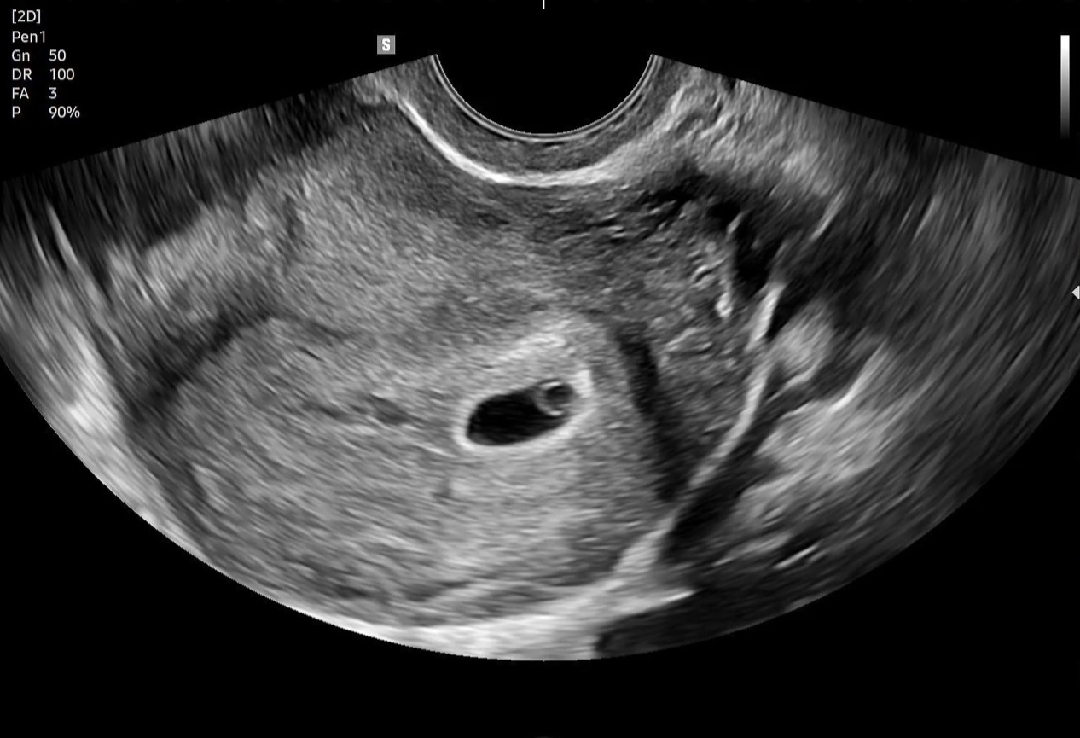

아기집 보고 왔어요🩷

역전 전이라서 이번에도 안보일까 걱정했는데 다행히 난황까지 잘 보고 왔네요ㅎㅎㅎ 아직 갈길이 멀지만 확인하고 나니 한결 마음이 편해졌어요💕💕 5주 0일쯤 되는 극초기래요😆